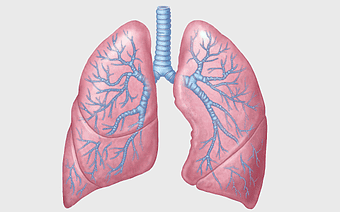

human lungs illustration, respiratory system anatomy, carina of trachea, blood vessel in lungs, pulmonary function, respiratory tract diagram, bronchial tree structure -

lung anatomy, respiratory system illustration, pulmonary alveoli structure, trachea and bronchi, human lung function, diaphragm movement, breathing process diagram -

human lung anatomy, trachea and bronchus, biomedical illustration, chest radiography, respiratory system diagram, pulmonary structure, medical imaging analysis -

Human Respiratory System illustration, pulmonary anatomy, trachea structure, respiratory organ function, bronchial tree, alveoli exchange, thoracic cavity -